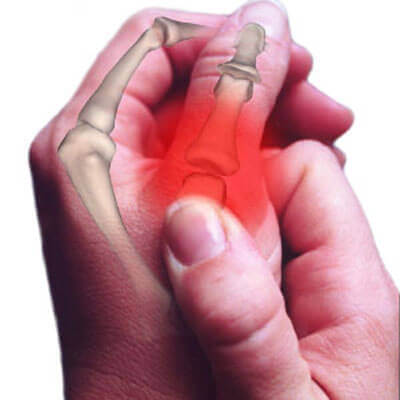

Het is goed om te onthouden dat onze gewrichten de contactpunten zijn waar onze botten samenkomen en ze zijn bedekt met een dikke ‘synoviale‘ vloeistof. Wanneer bijvoorbeeld een vingergewricht uitgerekt, gebogen of gekraakt wordt, dan scheidt het gewricht.

De gas-bubbel die in de gewrichtsholte zit wordt uitgerekt en is daardoor groter, wat de druk verlaagt. Wanneer dit gebeurt beginnen de opgeloste gassen bubbels te vormen in het synoviale slijm. Vervolgens ‘ontploffen’ ze, wat het bekende knakkende geluid veroorzaakt.

Men ontdekte tijdens dit onderzoek dat de vingers tekenen van schade lieten zien. Zoals beschadigingen aan het zachte weefsel en een verminderde mogelijkheid om dingen vast te houden. Dit lijkt gerelateerd te zijn aan de snelle en repetitieve uitrekking en samentrekking van de ligamenten van het gewricht.

Dit kan niet alleen leiden tot afbraak van de gewrichten, maar het vergroot ook de kans op gebroken botten. Andere gevolgen zijn: